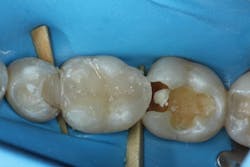

A patient presented with two failing composite restorations on teeth Nos. 30 and 31 (figure 1). A DermaDam rubber dam (Ultradent Products) was placed. This rubber dam was used because it has adequate thickness to displace tissue, yet sufficient compliance to stretch over larger clamped teeth without tearing. Rubber dam placement is used for only about 12% of operative dentistry procedures.1 Placing a rubber dam not only prevents salivary contamination of adhesive bonding procedures, but it also filters discarded dental materials, displaces the tongue and cheek, and reduces dental mirror condensation. The additional time required to place the rubber dam can be easily compensated for by these time-saving advantages, particularly when working on multiple restorations.

Figure 1: Initial presentation of failing composites on teeth Nos. 30 and 31

After removing the previous restorations, the distal axial wall of tooth No. 30 and the mesial axial wall of No. 31 had deep caries (figure 2). TheraCal LC (Bisco Dental)—a light-cured, resin-based liner containing calcium silicate (the active ingredient of MTA)—was placed over these areas of deep caries. A thin layer of the material was placed just at the areas of deep caries (figure 3) and light cured. Layers should be kept thin to ensure that the entire bulk of this opaque material cures, and placement should be limited to areas where needed in order to use the surrounding dentin for adhesive bonding. The dentin should be moist but not overly wet when TheraCal LC is applied to ensure that the material “sticks” to the tooth. Because this material is resin based, it is not necessary to cover this material with a separate resin-modified glass ionomer (RMGI) liner.

Figure 2: Deep caries remains on the distal axial wall of tooth No. 30 and the mesial axial wall of No. 31